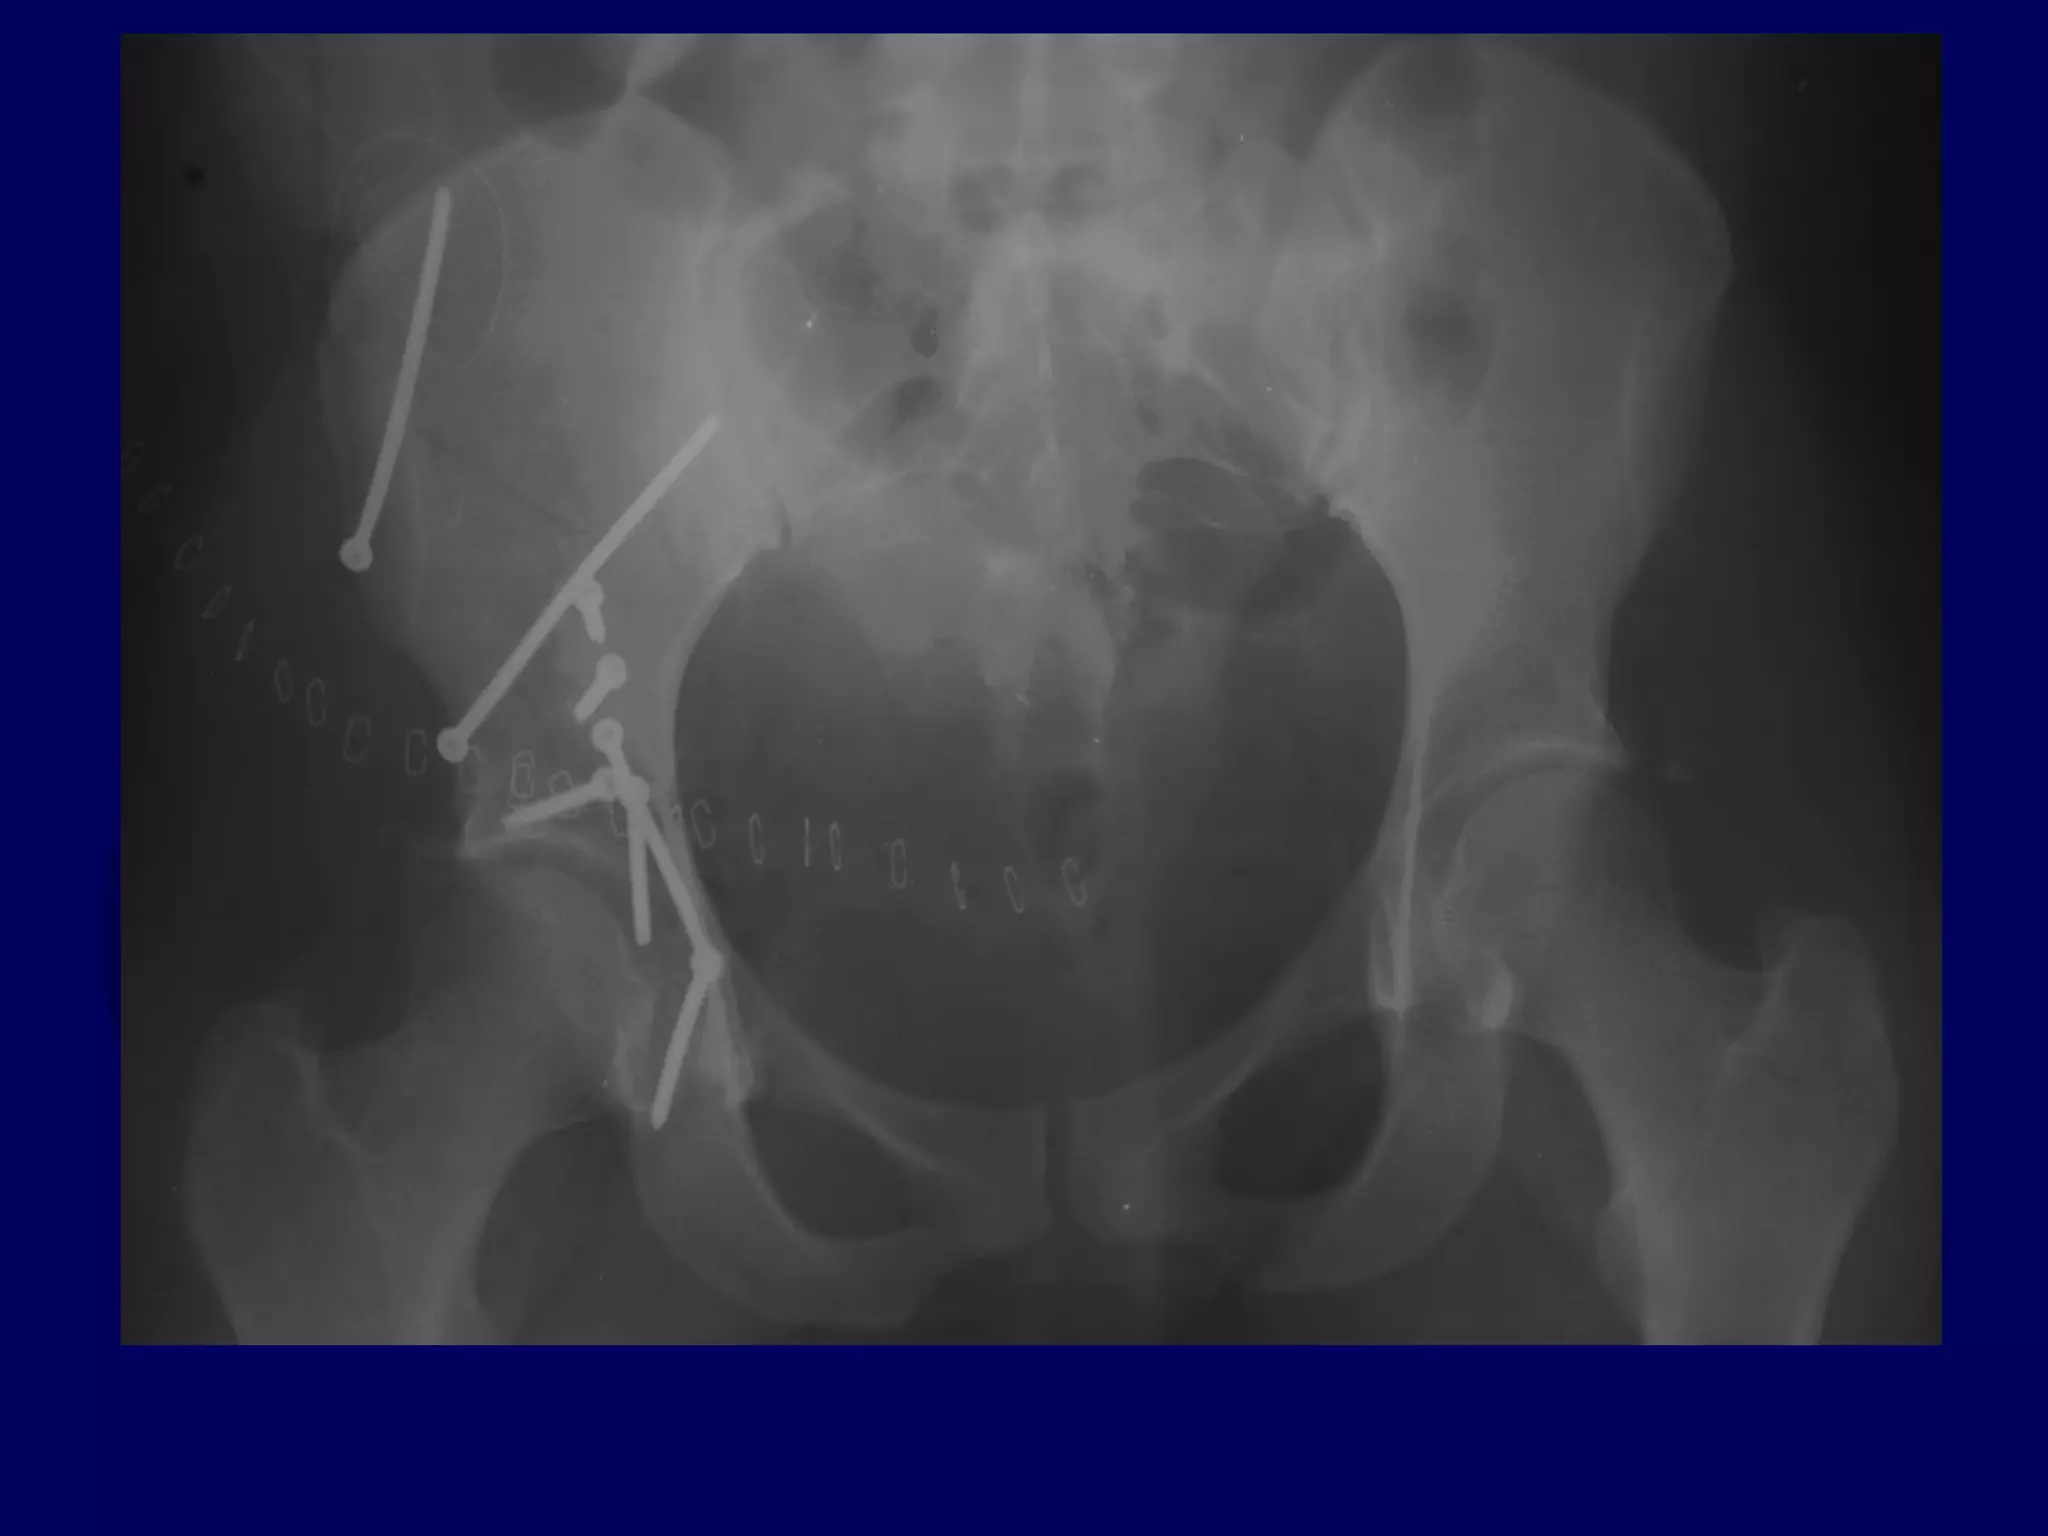

Both Column

Acetabular Fracture

18 Y.O. Female

Isolated Injury

Completion of Iliac Fracture

Reduction of Anterior Column

to Intact Ilium

Reduction of Posterior Column

INTACT ILIUM

R.C. 00.03.10